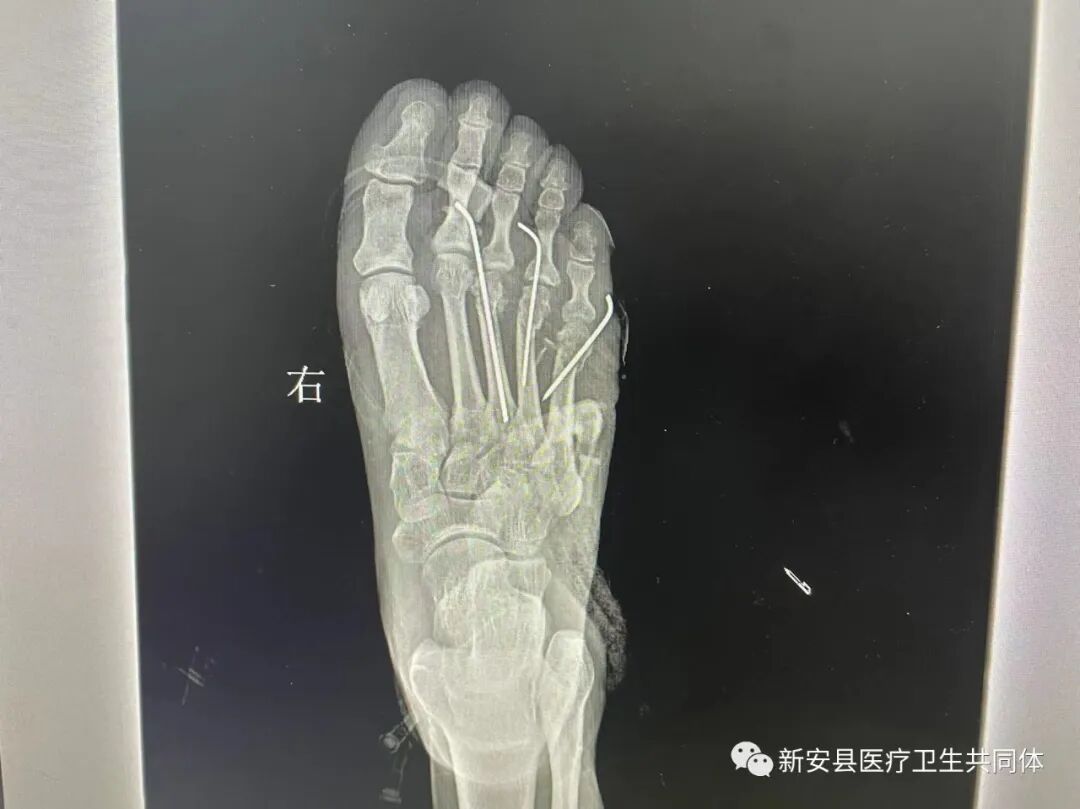

患者王某,男,69岁。因“右足外伤术后感染伴皮肤缺损”被收治到新安医共体第二人民医院手足伤病治疗中心。因两周前骑电动三轮车回家时,车翻后致伤头部及双下肢、右足部多处挫裂损伤。家人急送到附近医院给予患肢清创缝合及头面部的治疗,头面部伤情稳定后,发现右足部伤口感染伴皮肤及局部组织缺损约5.5*4.0cm,足背红肿明显,缺损创面脓性分泌物较多并伴有腱性组织和骨质外露,患足远端活动障碍。右足X线检查发现右足第三、四、五跖骨骨折,遂到新安医共体第二人民医院继续治疗。

入院后完善各项检查,在科主任刘守彬及张继宾大夫和科室医护团队的极力协作下,经过应用创面封闭冲洗--VSD负压技术治疗后,患足感染很快得到控制,创面肉芽组织生长良好。患足骨折给予切开复位应用克氏针内固定。缺损创面在小腿内侧切取一中厚皮片行植皮术,术后植皮成活,患肢创面完全覆盖愈合。右足X线检查见骨折内固定复位及愈合良好,目前已痊愈出院。出院时患者及家属对手足伤病治疗中心的医护团队表示真心的感谢:“真的是太感谢您们了,家里人看到这么严重的伤情真的不知道怎么办了,幸亏咱县有专业的手足伤病治疗中心,在这么短的时间里就把我父亲的脚治好了!”